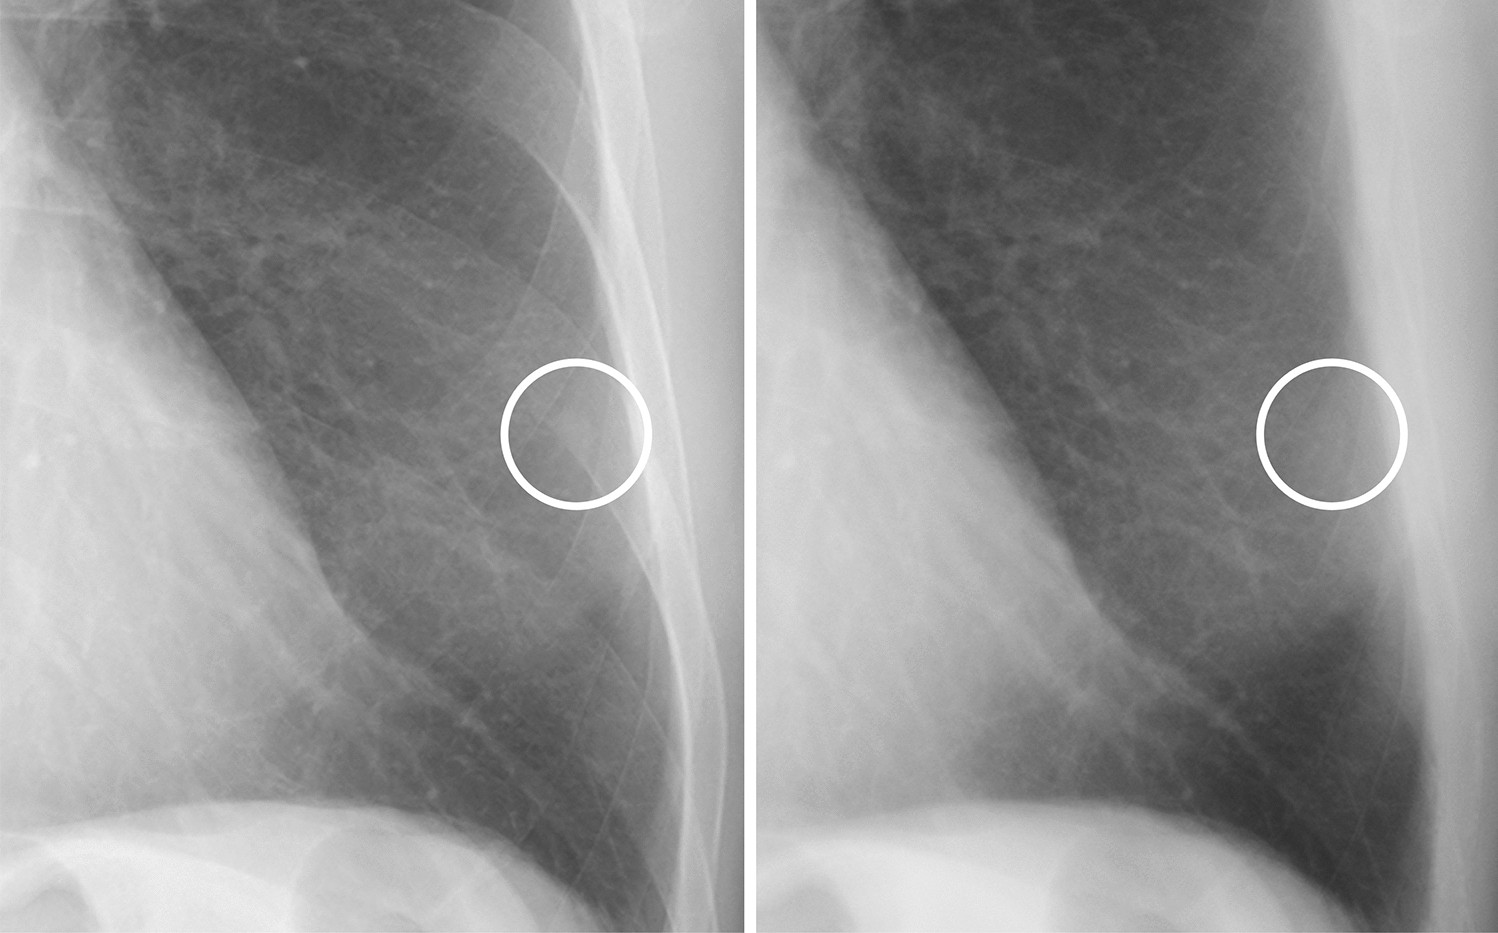

Figure 1

A case of a calcified nodule overlapping with the bone. (left) On the standard image, the evaluation of the presence or absence of calcification among readers was not consistent (confidence level of each reader: 4, 3, 3, 4 and 2, respectively). (right) In the soft tissue image, the nodule disappeared. All readers correctly evaluated it as calcified (confidence level of each reader: 1, 1, 2, 2 and 2, respectively).